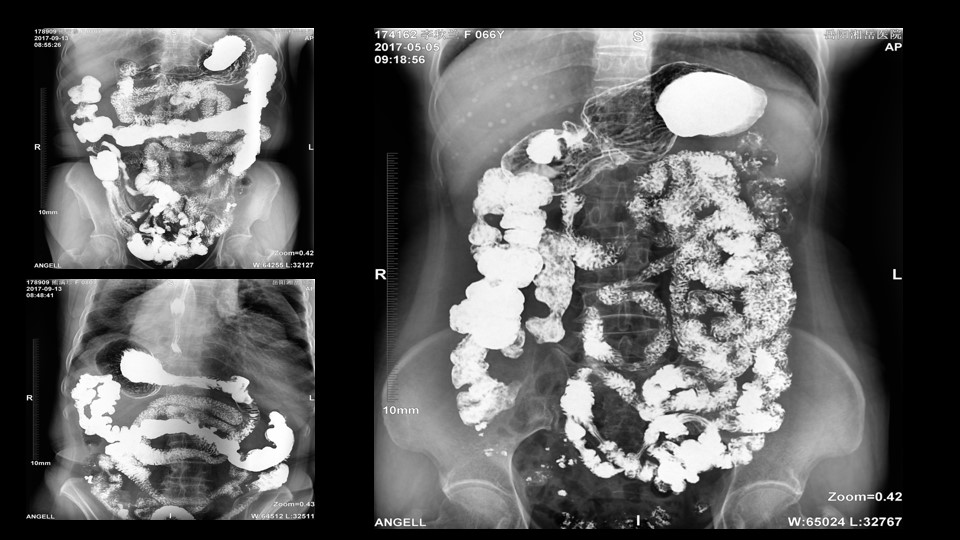

會議開始,岳陽市醫學會放射分會副主委、湘岳醫院放射科蔡雨主任,結合自身在放射影像的20多年經驗,為參會嘉賓分享了動態DR在消化道造影中的應用價值。作為動態DR用戶,蔡雨主任結合動態DR的實際拍片與操控經驗,分享了動態DR技術在相關群體疾病檢查上的獨到優勢和人文關懷。蔡雨主任說到:“隨著內鏡技術的發展以及CT、MR的發展,消化道造影在減少,但是這并不意味著消化道造影的價值在下降。以老年人為例,很多老年群體都患有嚴重的心肺疾病、或者消化道畸形,很多老年人本身就有糖尿病、高血壓等等綜合疾病,傳統內鏡的檢查對于這類群體來說是一件難以忍受的痛苦,而動態DR的多項創新技術讓這類群體的消化系統疾病篩查變得更為人性和精準。任何一個好的消化道造影,一定是患者、診斷醫生、臨床醫生三方滿意的結果。安健科技動態DR技術利用900萬像素高清拍片、大幅面透視、高清點片、視頻保存與回放等核心功能,完全滿足臨床對消化道氣鋇雙重造影檢查的需要。圖像質量全面超越以往模擬胃腸機、影增數字胃腸機”。蔡雨主任全面演示了動態DR在食道造影、上消化道造影、小腸雙對比造影、結腸氣鋇雙對比造影中的應用,通過動態DR可以清晰獲得臨床診斷和評估的圖像依據。

蔡雨主任使用動態造影圖像示例